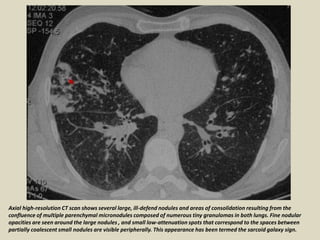

Small satellite nodules are often identified at the periphery of these masses,

giving an appearance that has been termed the "sarcoid galaxy sign".

Axial high-resolution CT scan shows several large, ill-defend nodules and areas of consolidation resulting from the

confluence of multiple parenchymal micronodules composed of numerous tiny granulomas in both lungs. Fine nodular

opacities are seen around the large nodules , and small low-attenuation spots that correspond to the spaces between

partially coalescent small nodules are visible peripherally. This appearance has been termed the sarcoid galaxy sign.